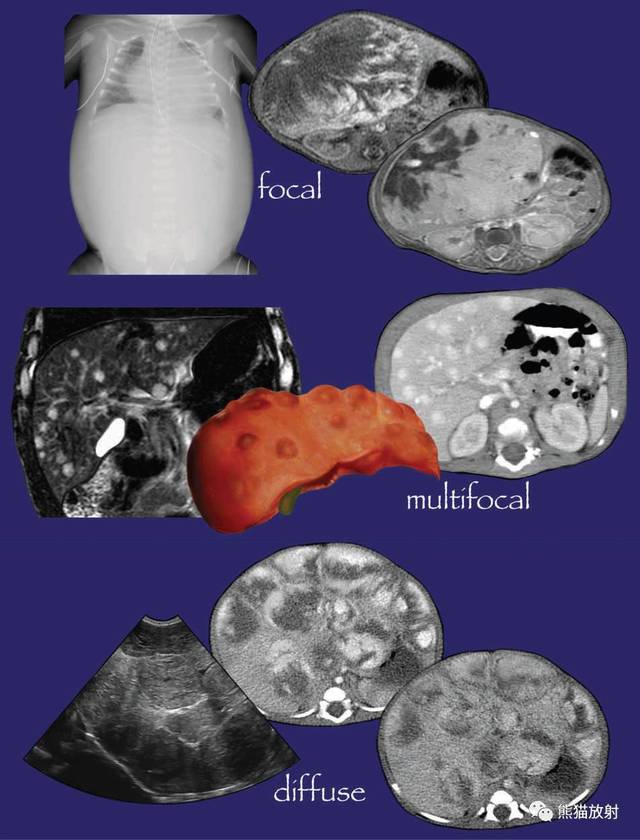

从形态上看肝血管瘤分小毛细血管瘤和巨大肝血管瘤。毛细血管瘤小于5厘米,巨大肝血管瘤大于5厘米。按照分型可分肝海绵状血管瘤、肝硬化性血管瘤、肝毛细血管瘤、肝血管内皮细胞瘤。

儿童期的肝血管瘤多为先天性,呈多发性。巨大肝血管瘤可引起心力衰竭,如不治疗危及生命。可行瘤血管栓塞及药物治疗。效果不好可选择手术。